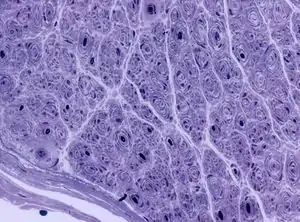

| Onion bulb formations in a nerve biopsy in a case of HMSN type I | |

Hereditary motor and sensory neuropathies (HMSN) is a name sometimes given to a group of different neuropathies which are all characterized by their impact upon both afferent and efferent neural communication. HMSN are characterised by atypical neural development and degradation of neural tissue. The two common forms of HMSN are either hypertrophic demyelinated nerves or complete atrophy of neural tissue. Hypertrophic condition causes neural stiffness and a demyelination of nerves in the peripheral nervous system, and atrophy causes the breakdown of axons and neural cell bodies.[1] In these disorders, a patient experiences progressive muscle atrophy and sensory neuropathy of the extremities.[2]